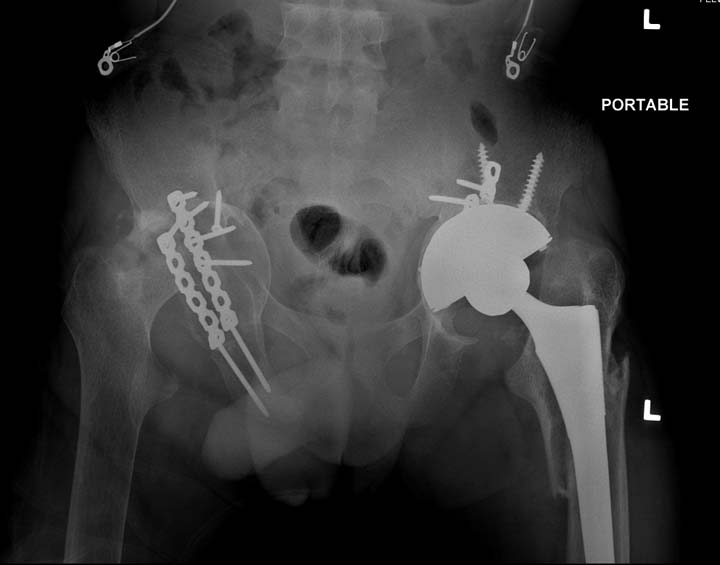

Больному 25 лет, транспортная травма. С детства хроническая почечная

недостаточность, постоянный гемодиализ, находится в листе ожидания на

пересадку почки. Около 4 года назад автоавария с двухсторенним переломом

ацетабулум, которая слева закончилось тотальным протезированием.

Диагноз: переломы бедренных костей, перелом дистального плеча слева,

также неосложненный перелом на уровне грудных позвонков.

Имя     : 2 Periprosthetic IM nail Lt femur.jpg